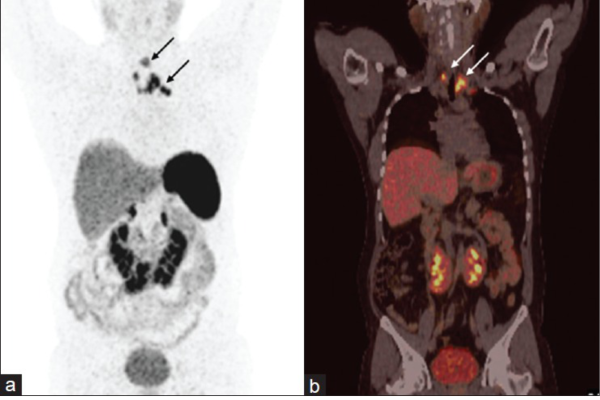

68-Ga DOTANOC PET-CT is an advanced nuclear imaging technique specifically designed for the detection and evaluation of neuroendocrine tumors (NETs). It works by targeting somatostatin receptors, which are commonly overexpressed in these tumors. This scan provides high-resolution images that help in localizing the primary tumor, assessing the extent of disease spread, and evaluating suitability for treatments like Peptide Receptor Radionuclide Therapy (PRRT). It is particularly valuable in managing gastroenteropancreatic tumors, paragangliomas, pheochromocytomas, and other NET-related conditions.

Key Indications:

• Gastroenteropancreatic tumors (Carcinoids, Insulinomas)

• Pheochromocytoma and Paraganglioma

• Medullary thyroid carcinoma

• Meningioma and other neuroendocrine tumors